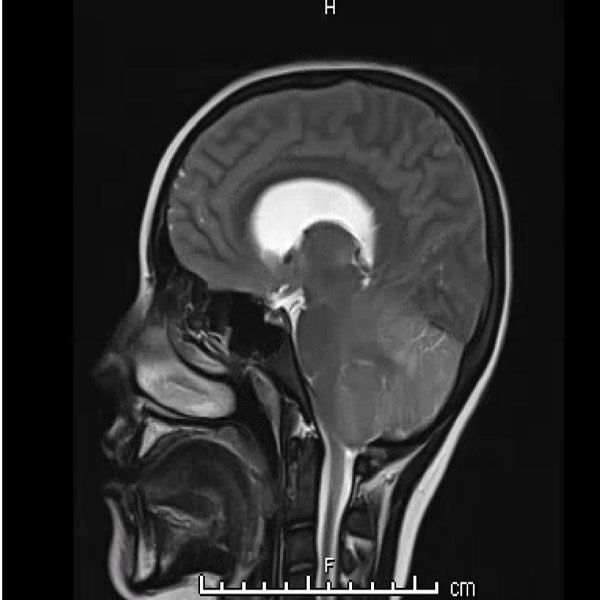

Urine toxicology, Tylenol level, Salicylate level, alcohol level thyroid studies, iron studies, hepatitis panel were normal. Urine pregnancy and COVID tests were negative. Head computed tomography (Head CT) showed mild hydrocephalus, and brain magnetic resonance imaging (MRI) showed increased signal folia and compression of the lower portion of the fourth ventricle and foramen of Magendie. She then had an emergency external ventricular drain placed (EVD) by pediatric neurosurgery, and the team started her on high-dose steroids and intravenous immunoglobulin (IVIG).

On the third day of admission, she developed new onset left-sided facial drooping, drooling, downbeat nystagmus, and difficulty following commands. An emergent subcortical craniectomy and decompression, duraplasty, and cerebellar biopsy were performed. A cerebellar biopsy was performed due to findings on brain MRI.

Consults were placed with pediatric neurology, pediatric infectious disease, pediatric hematology. Etiologies considered, included infectious, heavy metal poisoning, autoimmune, metabolic, and oncologic, with the following studies ordered: Cytomegalovirus Antibody(Ab) panel, and DNA, Coccidioides Ab, Epstein Barr Virus titers, fungal cerebrospinal fluid(CSF) panel, Human Immunodeficiency Virus testing, mycoplasma pneumoniae Ab, tuberculosis testing, toxoplasma Ab, meningitis panel, lactate dehydrogenase , uric acid, blood smear, CSF cytology, heavy metal panel, lead level, hemoglobin electrophoresis, complete blood count, complete metabolic panel, anti-nuclear Ab, N-Methyl-D-Aspartate receptor Ab, and ammonia. Lhermitte-Duclos disease versus cerebritis were also considered based on clinical status and radiological findings on brain MRI (Table 1).

Her biopsy result had nonspecific findings not consistent with Lhermitte-Duclos disease which is an extremely rare tumor of the cerebellum (dysplastic cerebellar gangliocytoma). The final diagnosis was lead encephalopathy.